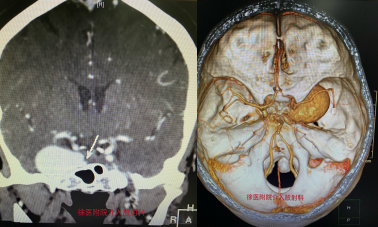

患者王阿姨因右眼腫脹3月余至當(dāng)?shù)蒯t(yī)院就診,檢查發(fā)現(xiàn)顱內(nèi)血管占位,考慮巨大動脈瘤可能性大。轉(zhuǎn)至徐醫(yī)附院后,介入科徐浩主任、崔艷峰主任立刻組織醫(yī)療團(tuán)隊對患者進(jìn)行頭頸部CTA及腦血管造影檢查,檢查結(jié)果令人吃驚。這是一例較罕見的巨大頸內(nèi)動脈海綿竇段動脈瘤,瘤體大小約34mm*24mm,治療過程中一旦破裂出血,死亡率極高。

對于巨大顱內(nèi)動脈瘤,傳統(tǒng)支架輔助下彈簧圈填塞或者封閉載瘤動脈都會對患者產(chǎn)生不良影響,復(fù)發(fā)率高,易產(chǎn)生腦缺血并發(fā)癥。徐浩主任、崔艷峰主任攜團(tuán)隊成員仔細(xì)研判病情并深入討論后決定使用較為前沿的血流導(dǎo)向支架技術(shù)。血流導(dǎo)向支架(Pipepline支架)是一種低網(wǎng)孔率和高金屬覆蓋率支架,可改變血流方向并促進(jìn)支架內(nèi)的內(nèi)皮細(xì)胞增生,通過促使瘤頸內(nèi)膜化達(dá)到修復(fù)載瘤動脈的作用。該項(xiàng)技術(shù)是目前國際上較為先進(jìn)的治療復(fù)雜顱內(nèi)動脈瘤的主要治療手段。